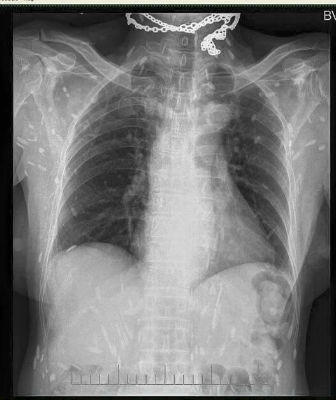

Rùng mình trước hình X - quang của người mê... ăn sống

(PLO) - Mấy ngày gần đây, cộng đồng mạng chia sẻ các bức ảnh chụp X-quang rất khủng khiếp của một bệnh nhân nhiễm sán. Theo đó, trên các bức ảnh X-quang là la liệt các xác sán xơ mít có đầu vôi hóa hình như hạt gạo. Theo các bác sĩ, nguyên nhân bị nhiễm sán là do ăn phải thức ăn sống như rau sống, tiết canh, gỏi cá… có nhiễm trứng, ấu trùng sán.

Bác sĩ Lương Quốc Chính - Bệnh viện Bạch Mai cho biết: “Rất nhiều người vẫn cho rằng đây không phải là hình ảnh của nhiễm sán vì không thể có chuyện sán lại cản quang trên phim X-quang được, nhưng vì đây là tổn thương đã vôi hóa nên mới cản quang như vậy, chỉ cần sử dụng hai từ khóa Cysticercosis, Trichinellosis để tìm ảnh trên trang tìm kiếm google sẽ thấy những hình ảnh tương tự”.